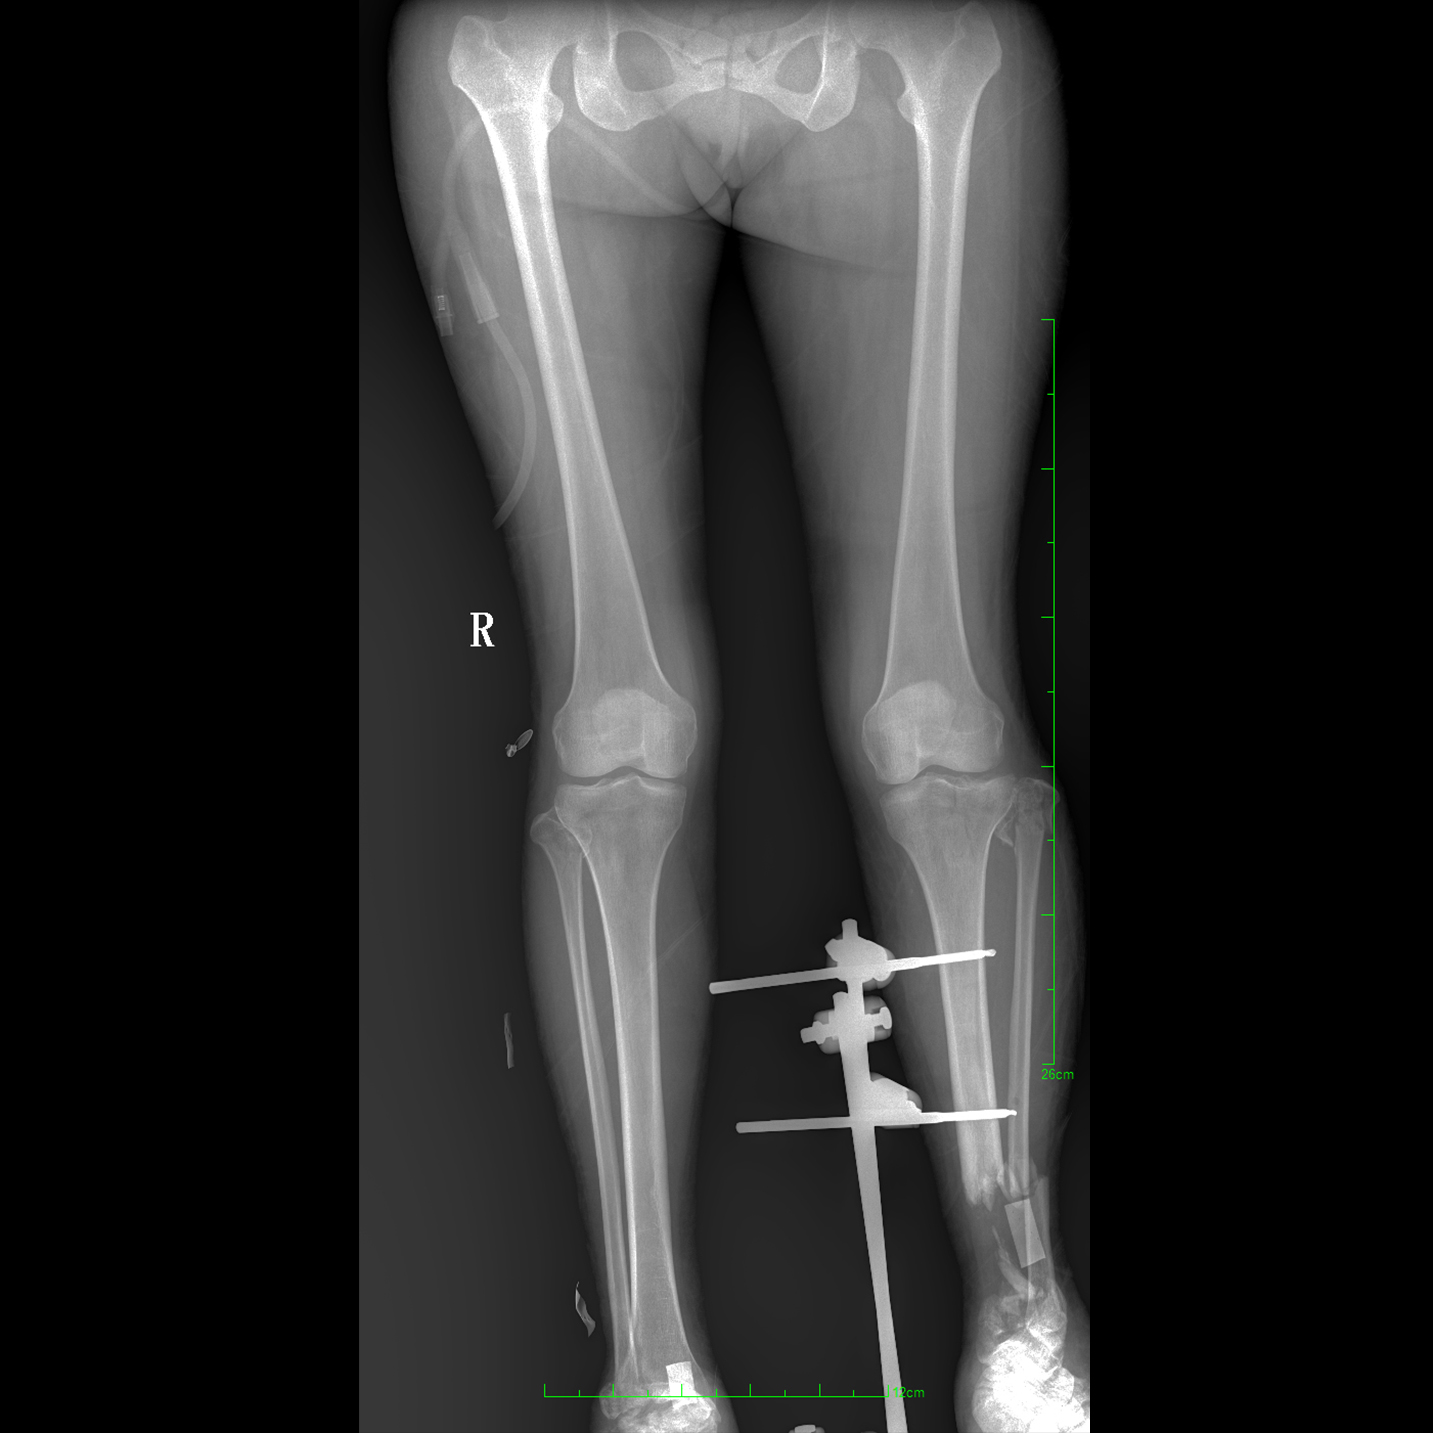

支持全脊柱攝影、雙下肢攝影、脊髓造影、復(fù)雜創(chuàng)傷、人工關(guān)節(jié)置換、關(guān)節(jié)損傷的修復(fù)重建等大視野臨床應(yīng)用

17"*34"有效視野,一次成像不拼接。相較于多張攝影再軟件拼接的DR設(shè)備,PLX8600解決了拼接圖像存在密度不均勻,拼接處圖像配準(zhǔn)和放大效應(yīng)等問(wèn)題,給臨床帶來(lái)了大視野影像解決方案,可一次性覆蓋全脊柱或雙下肢影像。

除常規(guī)靜態(tài)攝影外,PLX8600大平板具備動(dòng)態(tài)透視和點(diǎn)片功能,透視采集功能可支持大視野、多角度的可視化觀察。通過(guò)可視化的動(dòng)態(tài)影像,配合點(diǎn)片功能,能夠很好的觀察復(fù)雜部位病灶,有效的抓取關(guān)鍵幀,降低患者多次攝片的概率。如:全脊柱狀態(tài)評(píng)估、長(zhǎng)骨關(guān)節(jié)活動(dòng)度、下肢靜脈造影瓣膜功能評(píng)估、消化道功能評(píng)估、脊髓造影等更多大視野臨床應(yīng)用。